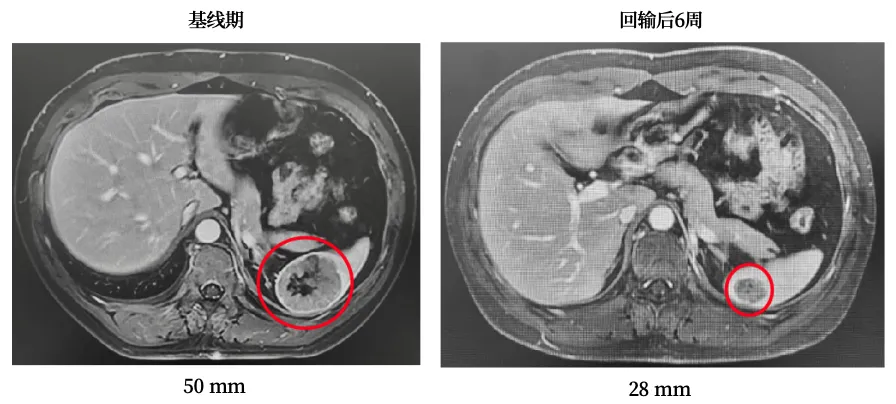

第一位ROS1融合阳性的晚期肺癌患者2020年5月确诊左肺低分化腺癌,先后接受克唑替尼、培美曲塞+卡铂+贝伐珠单抗联合治疗、恩曲替尼治疗,但病情始终无法控制,2024年10月发生脾脏转移,陷入无药可医的绝境。

接受单次TIL细胞回输后,仅出现短暂的一过性发热和血象降低,无其他不良反应。42天疗效评估时,肿瘤缩小33%,乳酸脱氢酶从2377 U/L骤降至258

U/L,身体状态明显好转。